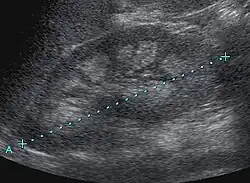

Sofern keine Nierenkoliken und keine Niereninsuffizienz vorliegen, handelt es sich oft um einen Zufallsbefund. Die Sonographie im Rahmen der Kindervorsorgeuntersuchung ist ein äußerst empfindliches Nachweisverfahren. Der Schweregrad der Veränderungen kann sonographisch unterteilt werden:[5]

- Grad I: geringe, ringförmige Echogenitätsvermehrung zwischen Markpyramiden und Nierenrinde

- Grad II: geringe diffuse Echogenitätsvermehrung der gesamten Markpyramide

- Grad III: ausgeprägte, homogene Echogenitätsvermehrung